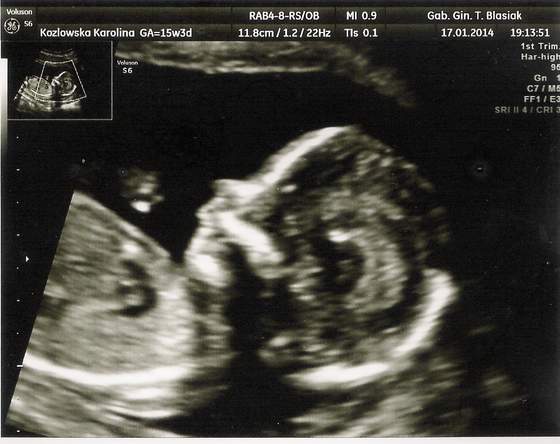

wizyty dzień do nocy, tamten na NFZ nic nie mierzył, tylko CRL a ten? Wszystkie kości pomierzył, paluszki policzył, główkę zmierzył, nawet mózg i móżdzek, serduszko dokładnie obejrzał ile komór, jak krew wpływa do serca, jak wypływa, posłuchaliśmy serduszka jak bije, czy budowa pępowiny jest ok, czy kręgosłup jest ok, jejku tyle rzeczy że aż nie mogłam się nadziwić, dostaliśmy chyba z 10 zdjęć z USG, i całą stronę A4 z opisami co badał, jakie są wyniki i czy jest ok. Najfajniejszy moment był jak przełączył na widok 3D i w tym samym czasie Maleństwo zakryło twarz raczkami tak jak małe dzieci się zakrywają i udają, że ich nie ma

niesamowite to było, aż wszyscy się zaczęliśmy śmiać :-)

oto kilka zdjęć naszej (chyba) córeczki